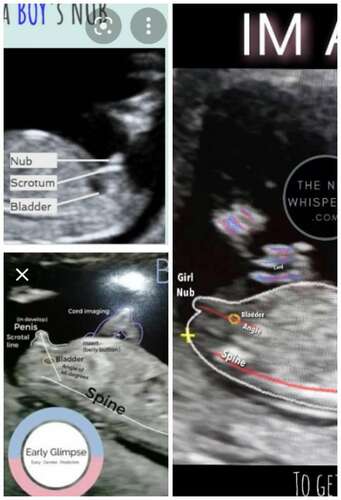

Met jouwn echo gok ik dat het een jongen in wording is. In wording omdat alles nog niet volledig op de plaats zit en dus in ontwikkeling zit. Waarom gok ik jongen?

Onderste foto is de nub van dichtbij.

Groen: de omranding van de kleine

Rood: de blaas

Blauw: de stand van nub en blaas in vergelijking met de ruggengraad

(📐) staat het in een hoek van de ruggengraad wijst het op een jongen.

(=) staat het gelijk of bijna gelijk aan de ruggengraad wijst het op een meisje.

Daarnaast is een bolletje boven de nub wat je bij jouwn echo hebt het deel wat langzaam de pipi word terwijl de lijn eronder langzaam veranderd in de balletjes. Bij meisjes zie je geen bolletje erboven daar is de nub een lijn. De blaas zal als het goed is nog iets verder zakken. Maar dat komt door het termijn waarin je zit dat het nog niet allemaal op de plek zit.